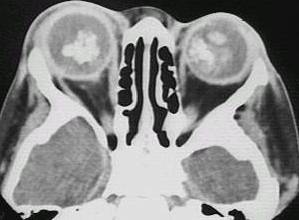

What type of image is it? CT scans or MRI scans (T1 or T2

weighted)

Which plane the image is in? axial, sagittal or coronal.

extraocular muscle enlargement (the main differetial

diagnosis include: thyroid eye disease if tendon is not involved or myositis

if the tendon is involved; other possibilities include neoplasm either

primary or secondary)?

space occupying lesion in the orbit: lacrimal

fossa (lacrimal gland tumour)? intraconal lesion (optic glioma, capillary

haemangioma or optic nerve meningioma)? diffuse lesion (lymphoma, metastatic

tumour or acute infection or inflammation)? dilated superior ophthalmic

vein (carotid-cavernous fistula)?